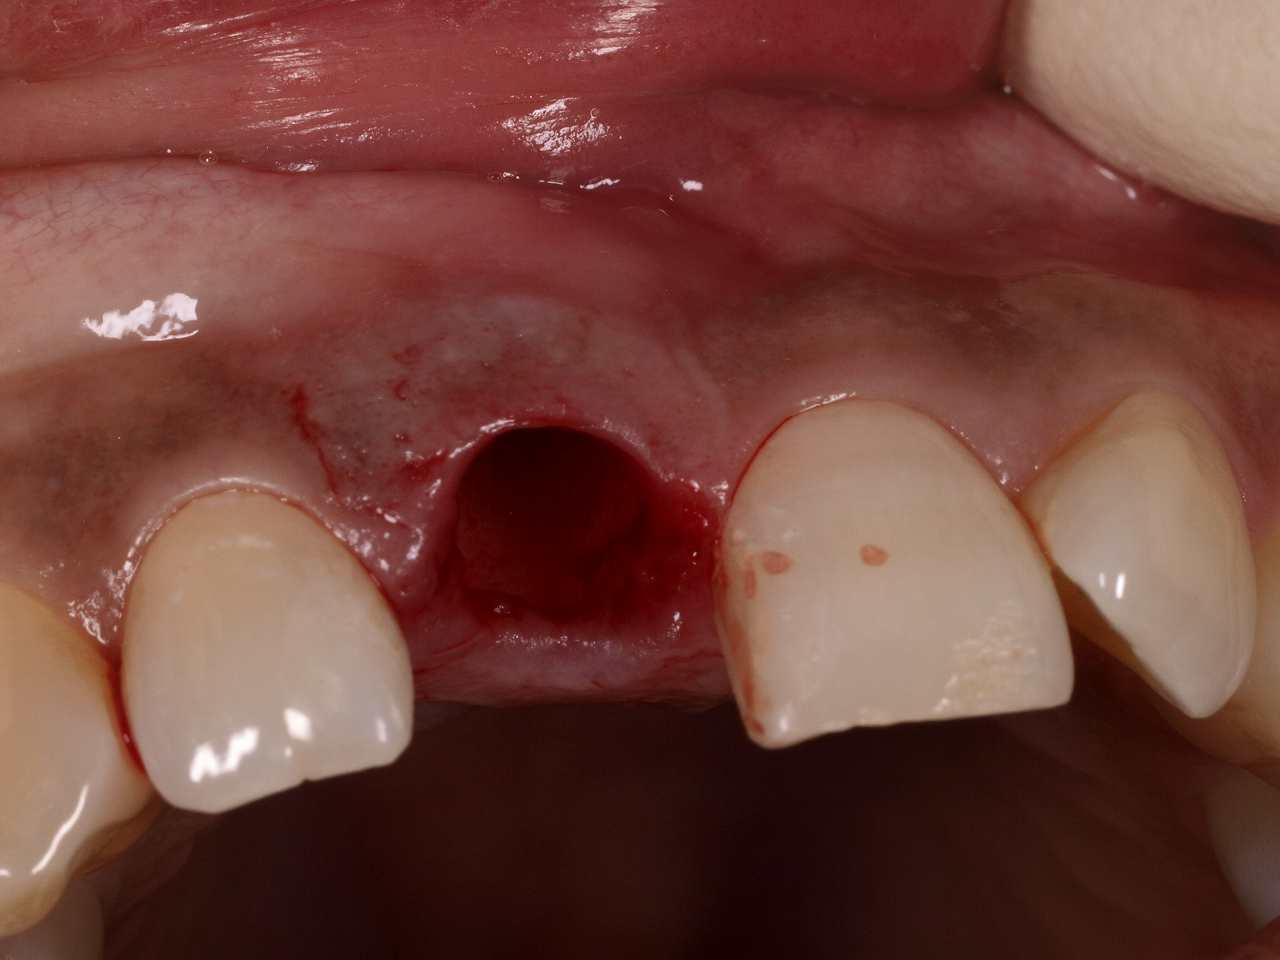

抜歯してインプラント埋入となりました

抜歯窩にインプラント埋入を行っていきました